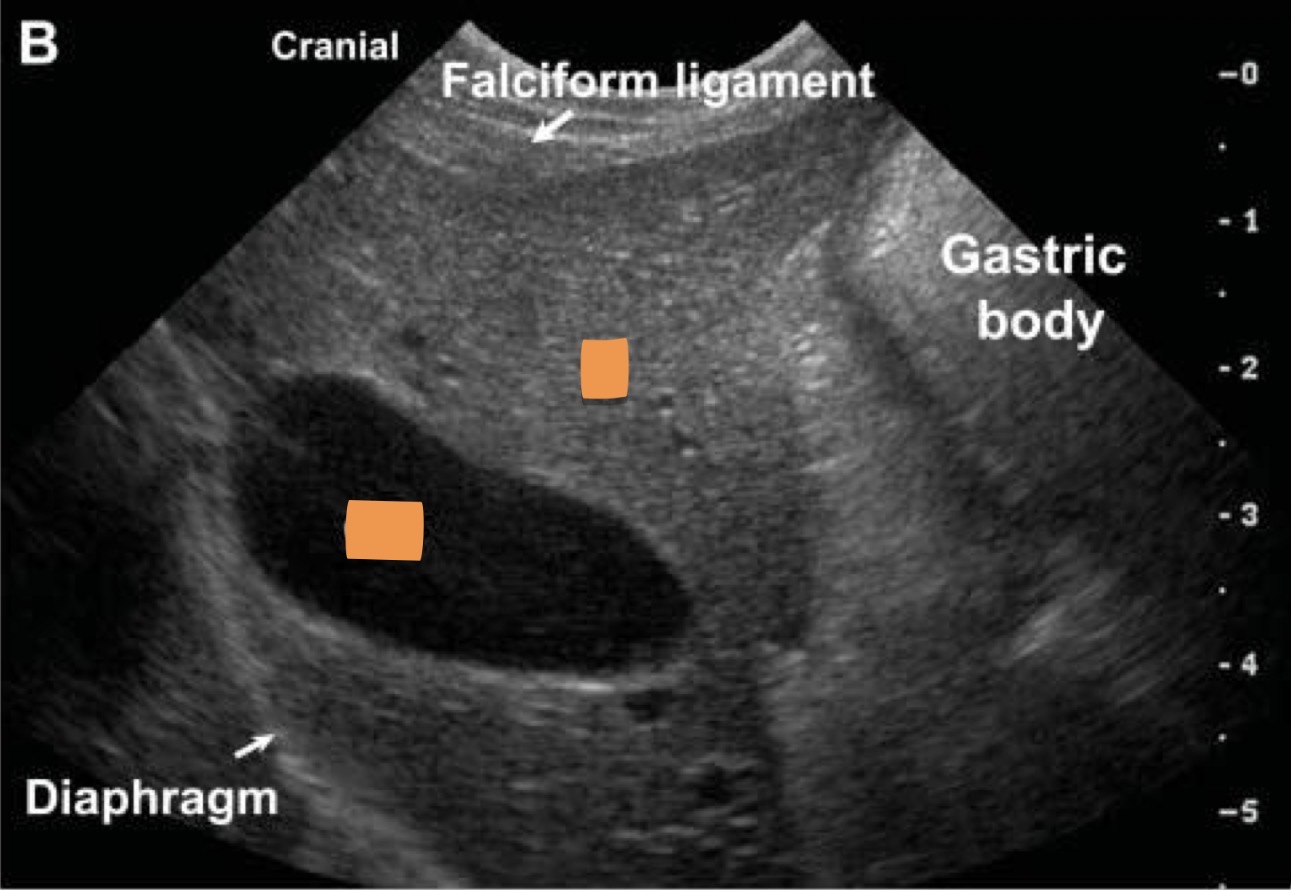

Left gall bladder

Right liver

What organs are marked?